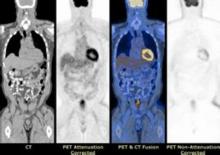

PET-CT的圖像融合

PET與CT兩種不同成像原理的設備同機組合,不是其功能的簡單相加。而是在此基礎上進行圖像融合,融合後的圖像既有精細的解剖結構又有豐富的生理.生化功能信息 能為確定和查找腫瘤及其它病灶的精確位置定量、定性診斷提供依據。並可用X線對核醫學圖像進行衰減校正。

PET-CT的核心是融合,圖像融合是指將相同或不同成像方式的圖像經過一定的變換處理 使它們的空間位置和空間坐標達到匹配,圖像融台處理系統利用各自成像方式的特點對兩種圖像進行空間配準與結合,將影像數據註冊後合成為一個單一的影像。 PET-CT同機融合(又叫硬體融合、非影像對位)具有相同的定位坐標系統,病人掃描時不必改變位置,即可進行 PET-CT同機採集, 避免了由於病人移位所造成的誤差。採集後兩種圖像不必進行對位、轉換及配準,計算機圖像融合軟體便可方便地進行2D、3D的精確融合,融合後的圖像同時顯示出人體解剖結構和器官的代謝活動, 大大簡化了整個圖像融合過程中的技術難度、避免了複雜的標記方法和採集後的大量運算,並在一定程度上解決了時間、空間的配準問題,圖像可靠性大大提高。

融合圖像PET在成像過程中由於受康普頓效應、散射、偶然符合事件、死時間等衰減因素的影響, 採集的數據與實際情況並不一致, 圖像質量失真,必須採用有效措施進行校正,才能得到更真實的醫學影像。同位素校正得到的穿透圖像系統解析度一般為12 mm、而 X線方法的穿透圖像系統解析度為1mm左右 圖像信息量遠大於同位素方法。用 CT圖像對 PET進行衰減校正 使 PET圖像的清晰度大為提高,圖像質量明顯優於同位素穿透源校正的效果, 解析度提高了 25%以上,校正效率提高了 30%,且易於操作。校正後的 PET圖像與 CT圖像進行融合, 經信息互補後得到更多的解剖結構和生理功能關係的信息 對於腫瘤病人手術和放射治療定位具有極其重要的臨床意義。